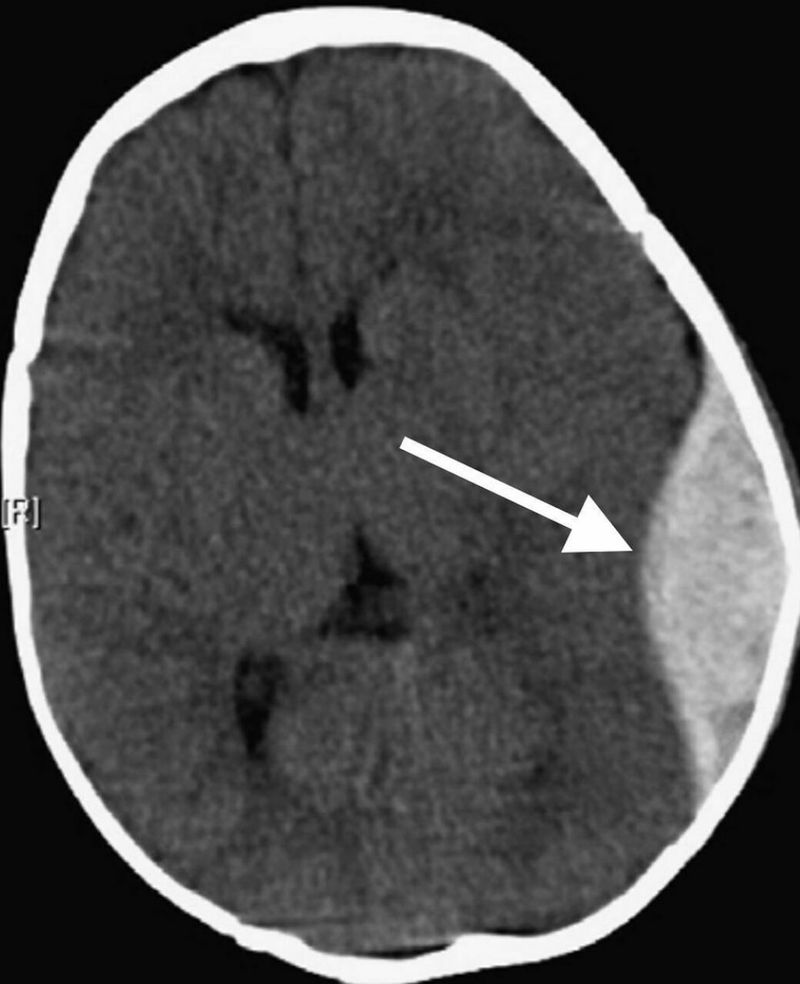

What is your due diagnostics

Epidural hematoma

I think on CT epidural hematoma is biconvex shaped but subdural hematoma is crescent shaped